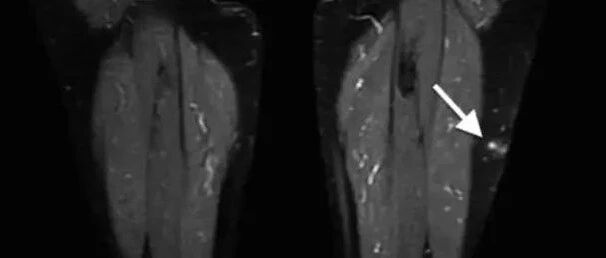

左前臂肿物,呈低回声,你考虑什么? 丁香园超声时间 · 公众号 · 医学 · 1 年前 · |